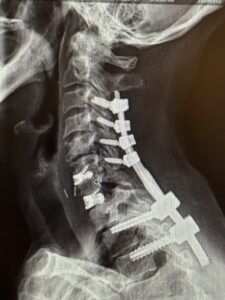

Her rheumatologist ordered an x-ray which showed anterolisthesis of C7-T-1 with kyphosis and instability (Fig 1 right).

The patient underwent a one-day, two-stage procedure. Stage 1 was a C6-7, C7-T1 anterior cervical discectomy and fusion with reduction of the anterolisthesis and correction of the kyphosis.

Stage 1 was immediately followed by Stage 2 which was extension of her posterior instrumentation and fusion from C3 down to T3. Neuro-navigation was used to assist with the difficult anatomy of the upper thoracic spine.